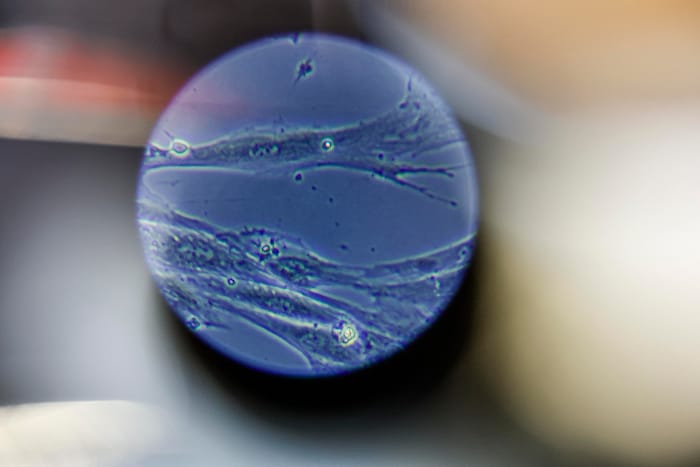

Blick ins Mikroskop: Vesikel sind Absonderungen von Zellen, die für Therapien genutzt werden ...

Blick ins Mikroskop: Vesikel sind Absonderungen von Zellen, die für Therapien genutzt werden sollen.(Bild: Markus Tschepp)